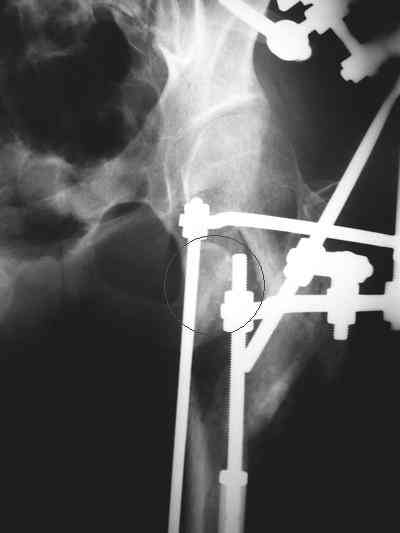

Девушка 21 года 02.10.07 г. пострадала в результате падения с высоты 4-го этажа при пожаре в одном из студенческих общежитий г. Москвы. Получила тяжелую сочетанную травму, в том числе закрытый оскольчатый чрез- и подвертельный перелом левой бедренной кости. Лечилась в одной из больниц столицы. Бедро было фиксировано при помощи скелетного вытяжения. Через полтора месяца после травмы переведена в институт им. Склифосовского. У больной имелись: поддиафрагмальный абсцесс, трахеопищеводный свищ, трахеостома, гастростома, несостоятельность швов раны передней брюшной стенки, укорочение левого бедра на 10 см (рентгенограммы при поступлении - рис 1.). В середине декабря был наложен спицестержневой аппарат, с помощью которого к сегодняшнему удалось устранить укорочение бедра (рис. 2). В течение последних 4-х дней устраняем смещение дистального отломка бедренной кости по ширине. Раны на передней брюшной стенке почти зажили. Температура тела и лабораторные показатели нормальные. Планируем выполнить закрытый остеосинтез левой бедренной кости удлиненным проксимальным бедренным штифтом производства фирмы "Остеомед". Нас смущает, что малый вертел бедренной кости остается значительно смещенным проксимально и кнутри.